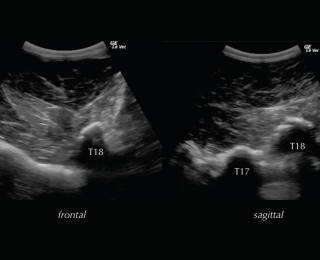

Deep to the ligament the fibrocartilaginous cap, visualised as a hypoechogenic line of approximately 1mm, is visible and runs parallel to the hyperechoic line of the DSP bone surface. The ISS cannot be assessed fully and a statement about potential iminging DSPs should not be made based on ultrasonography alone. The intervertebral articulations can be examined ultrasonographically, both in sagittal and frontal planes, using a convex transducer (Denoix 1999a; Reisinger and Stanek 2005).

The anatomy and ultrasonographic appearance of the joints change slightly from cranial to caudal. The mammillary process is more prominent in the thoracic spine and the joint is positioned further axial and closer to the DSP compared to the lumbar region. Signs of pathology in the intervertebral articulations (see Figure 4) include new bone formation and an enlarged outline of the facet (Denoix and Dyson 2003).